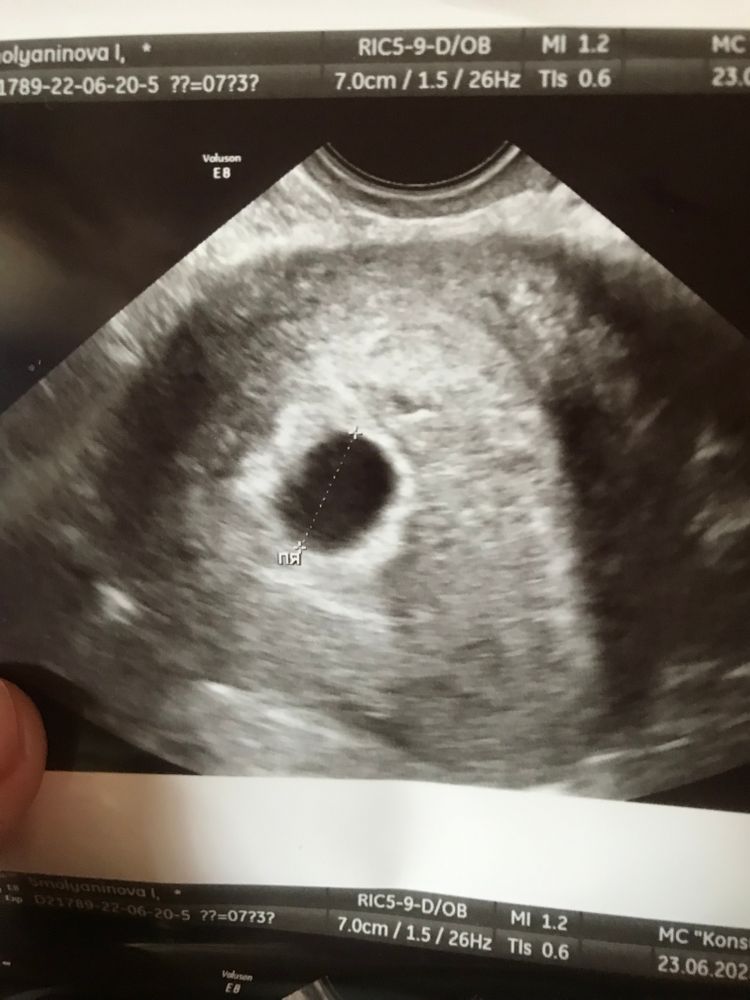

Ирина, у вас на снимке написаны размеры)

По мне так выглядит неплохо